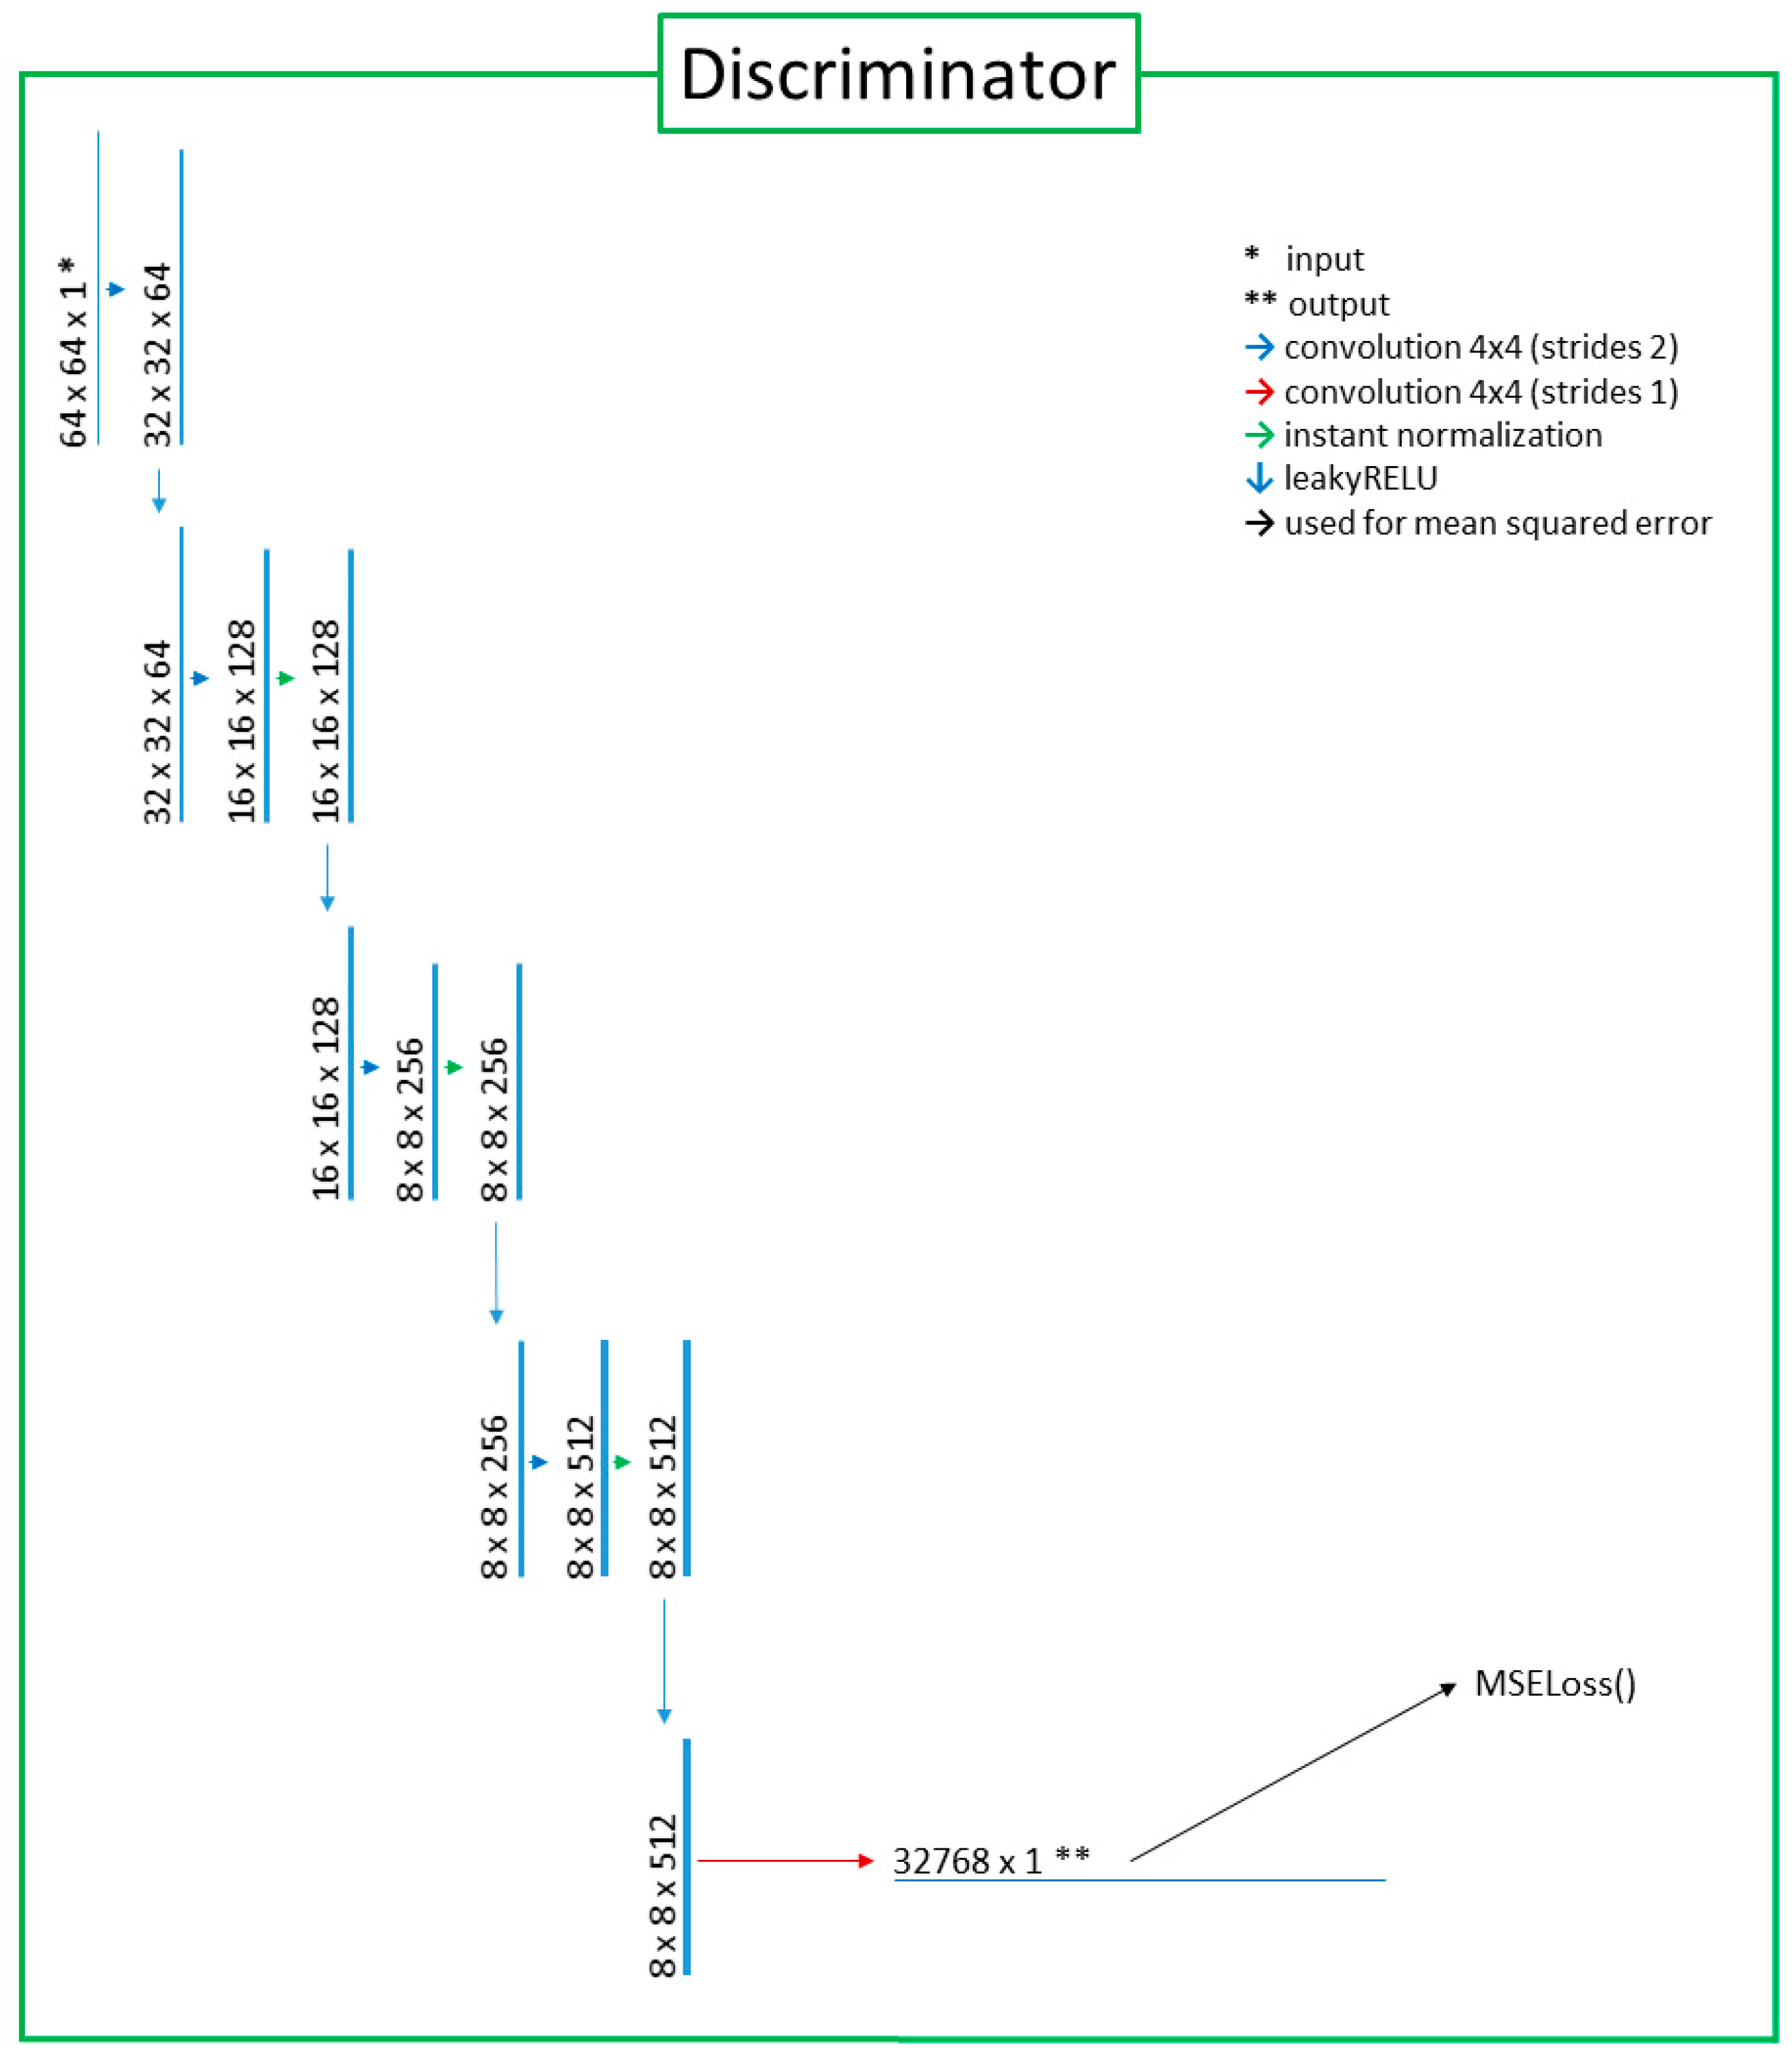

2.2. Deep-Learning Model with Image Preprocessing